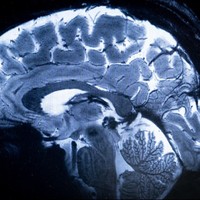

親指の長さ、脳の大きさとの関連性が判明 骨格成長に関わる遺伝子が幼少期の脳発達にも関与 ドイツ研究![]()